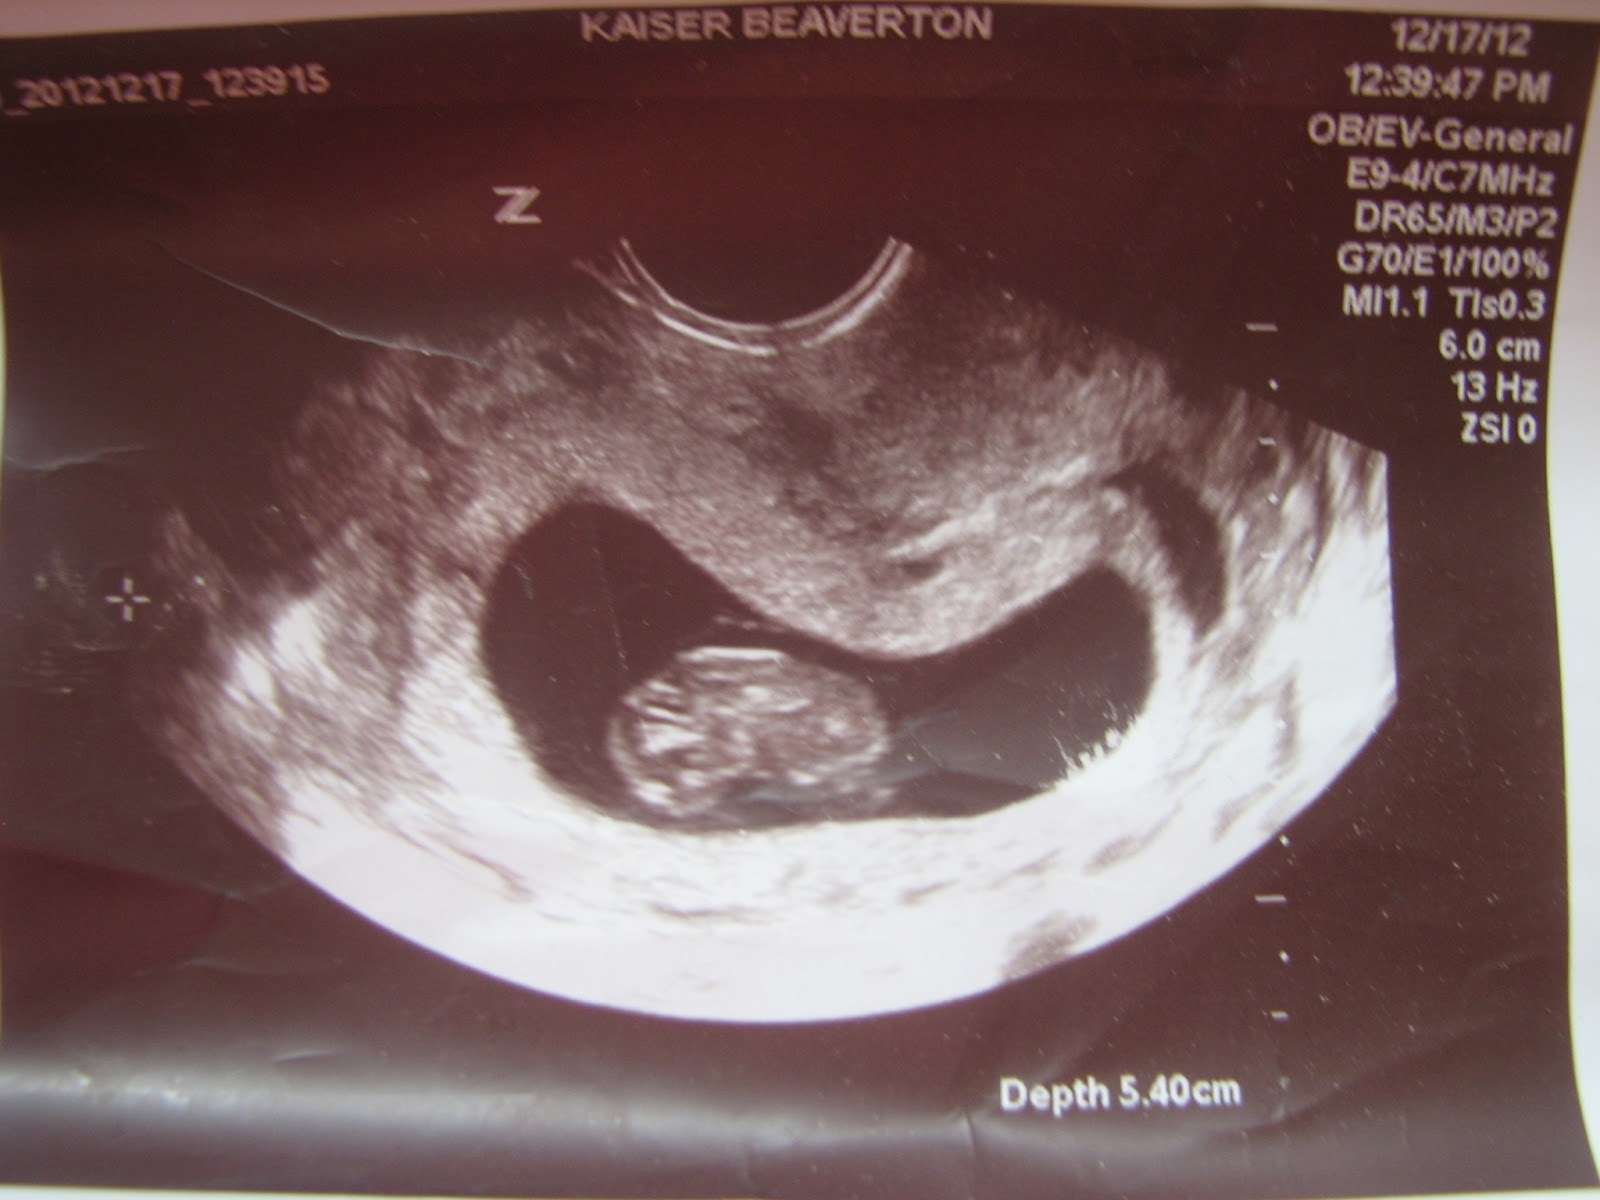

Around 16 weeks, I was feeling anxious about our baby.

While you eagerly wait during the ultrasound, keep in mind that you may not actually get to see the baby. I wasn’t feeling any symptoms, and it was definitely too early to feel any fetal movement. Around weeks pregnant, you’ll most likely have the most-anticipated screening you’ll get during pregnancy.It’s the Level 2 full-body anatomy scan, which is part of the second-trimester battery of screens, as well as an amazing opportunity to look at your baby.

Subscribe for more amazing content. All printed photos come with an instant digital delivery for free!. I was in the “quiet” weeks of pregnancy.